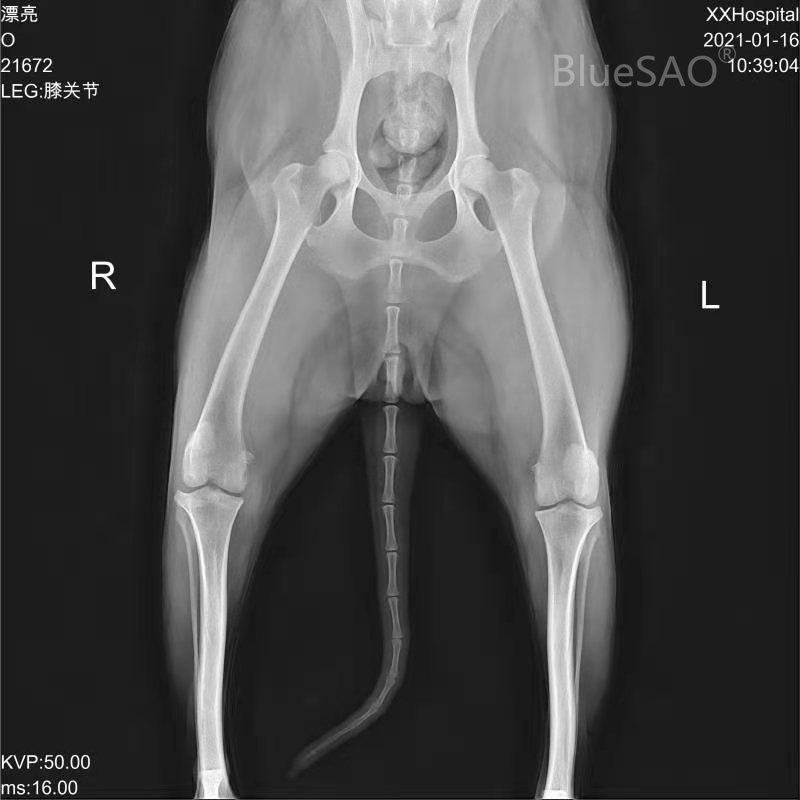

A Husky, 2 years old, female, 18Kg, went to the doctor due to lameness. The examination result showed that the drawer test was positiveand the cranial cruciate ligament rupture was found in the diagnosis. The planned TPA is 29 degrees before surgery and adjusted to 6 degrees after surgery. The BlueSAO TPLO-M8mm locking plate was used for TPLO surgery, the postoperative recovery was good, and the weight-bearing walking was already on the third day after the surgery. X-rays showed that the fracture line was blurred and healed well two weeks after thesurgery.